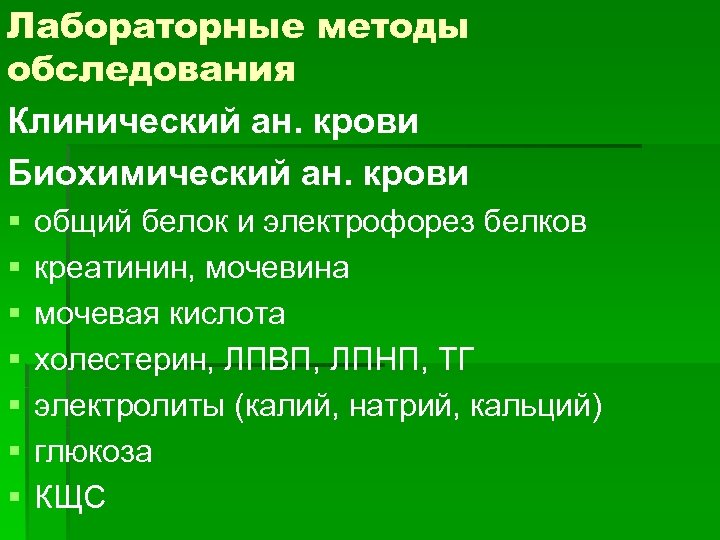

Лабораторные методы обследования Клинический ан. крови Биохимический ан. крови § § § § общий белок и электрофорез белков креатинин, мочевина мочевая кислота холестерин, ЛПВП, ЛПНП, ТГ электролиты (калий, натрий, кальций) глюкоза КЩС